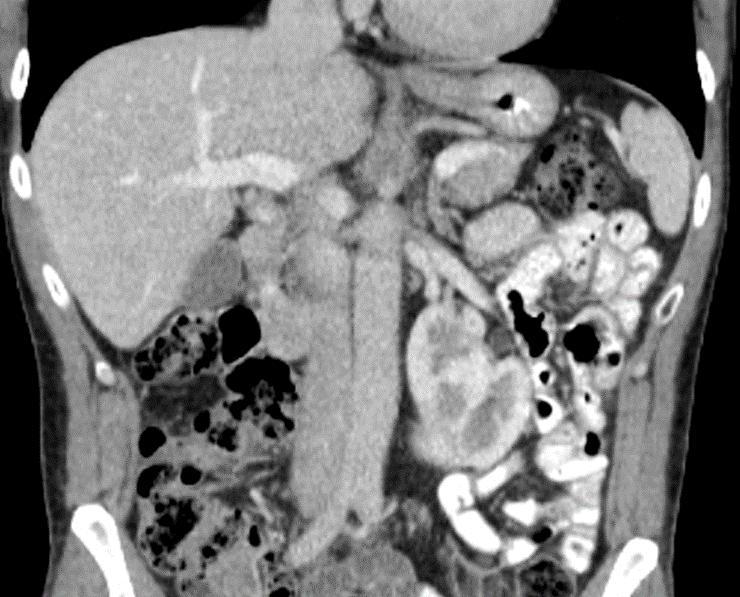

Obr. 1. Perioperační CT snímek během MWA.

Fig. 1. Perioperative CT scan during microwave ablation.

Výkon byl prováděn mikrovlnným systémem Solero Microwave Tissue Ablation System (AngioDynamics, Inc., USA). Během ablačních výkonů byla používána frekvence 2,45 GHz a výkon v rozsahu 100–140 W. Jako aplikátor byla používána nerezová ocelová jehla s keramickým hrotem o průměru 15 G a délce 14, 19 nebo 29 cm. Jedna ablační sekvence po zavedení jehly do tumoru trvá 4–6 min podle velikosti nádoru, v průběhu jednoho výkonu jsou standardně prováděny 1–2 ablační sekvence. Maximální velikost ablační zóny udávaná výrobcem je 54 × 39 mm na jednu sekvenci. Po skončení ablace tumoru se během vytahování jehly provádí ablace-koagulace punkčního kanálu (track ablace). Výkon je prováděn v analgosedaci za přítomnosti anesteziologa, pacienti snášejí výkon dobře. Celková doba výkonu vč. polohování pacienta a přípravy CT pracoviště je 60–90 min (obr. 1).